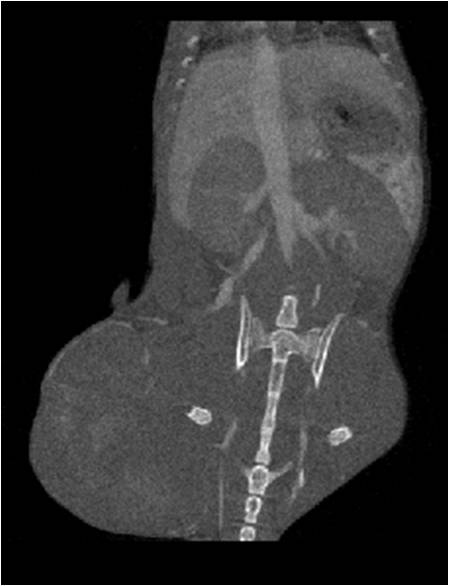

腫瘤血管生成

心血管

胸部和心血管的層析成像 胸部和心血管的3D圖像